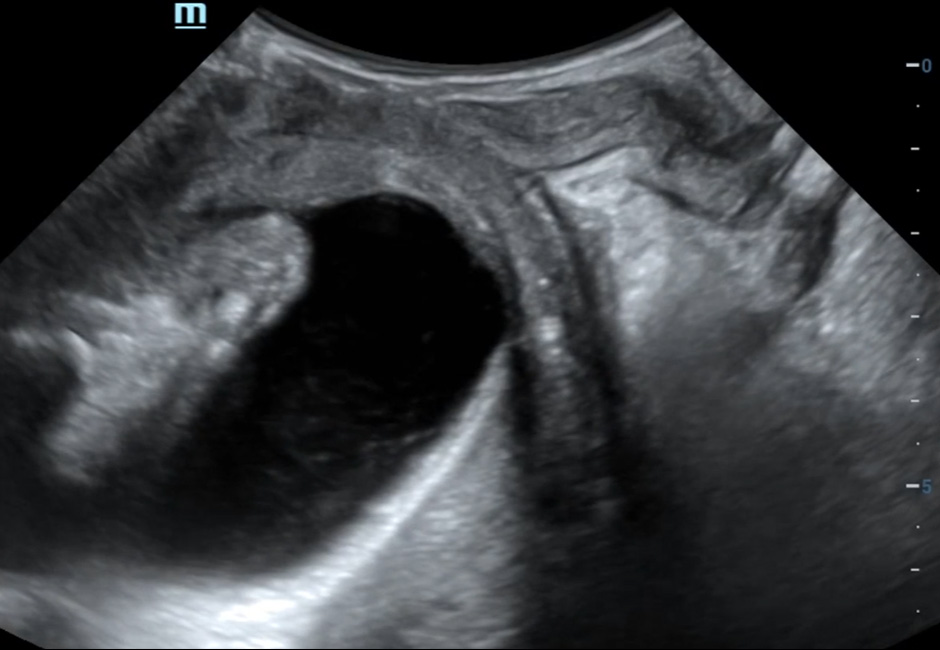

Levator ANI Avulsion

Green Classification of Cystocele-type I

-

Green Classification of Cystocele-type II